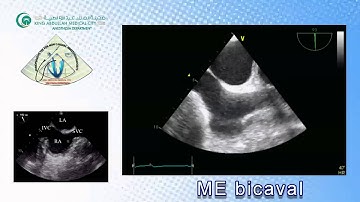

078 Basic View TEE KAMC